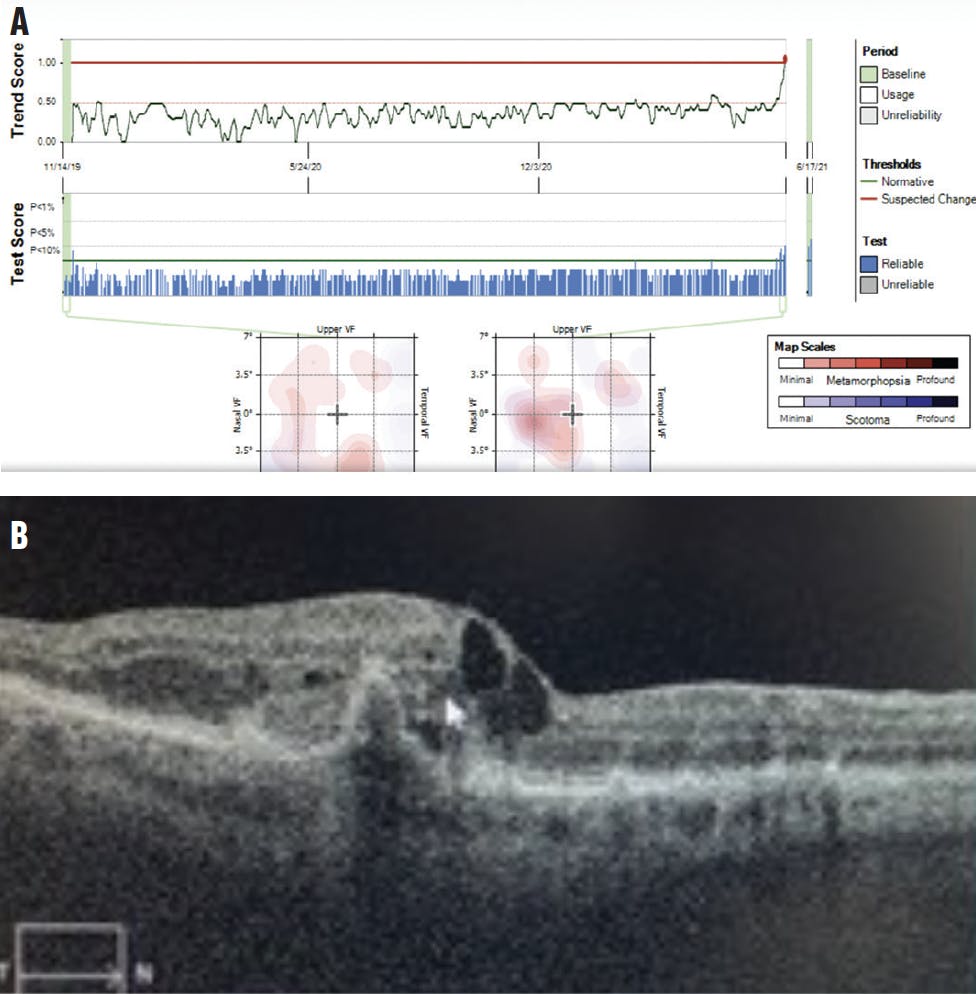

In June 2021, my office was alerted to changes to her at-home testing in the right eye. The patient was seen in the office the day after the alert—still with 20/20 vision—at which time she described metamorphopsia and blurred vision in her right eye that started about 1 week prior. Dilated fundus examination revealed new CNV with intraretinal fluid confirmed by OCT (Figure 6). She was diagnosed with conversion to wet AMD with active CNV in the right eye, received an intravitreal injection of anti-VEGF therapy, and was scheduled for monthly injections. She continued at-home monitoring for her left eye.

<p>Figure 6. Two months before the patient’s scheduled follow-up, the at-home monitoring program alerted the office to changes in her right eye testing (A). In-office examination confirmed extensive drusen, pigment epithelial detachments, and new choroidal neovascularization with intraretinal and subretinal fluid—conversion to wet AMD (B).</p>

Figure 6. Two months before the patient’s scheduled follow-up, the at-home monitoring program alerted the office to changes in her right eye testing (A). In-office examination confirmed extensive drusen, pigment epithelial detachments, and new choroidal neovascularization with intraretinal and subretinal fluid—conversion to wet AMD (B).